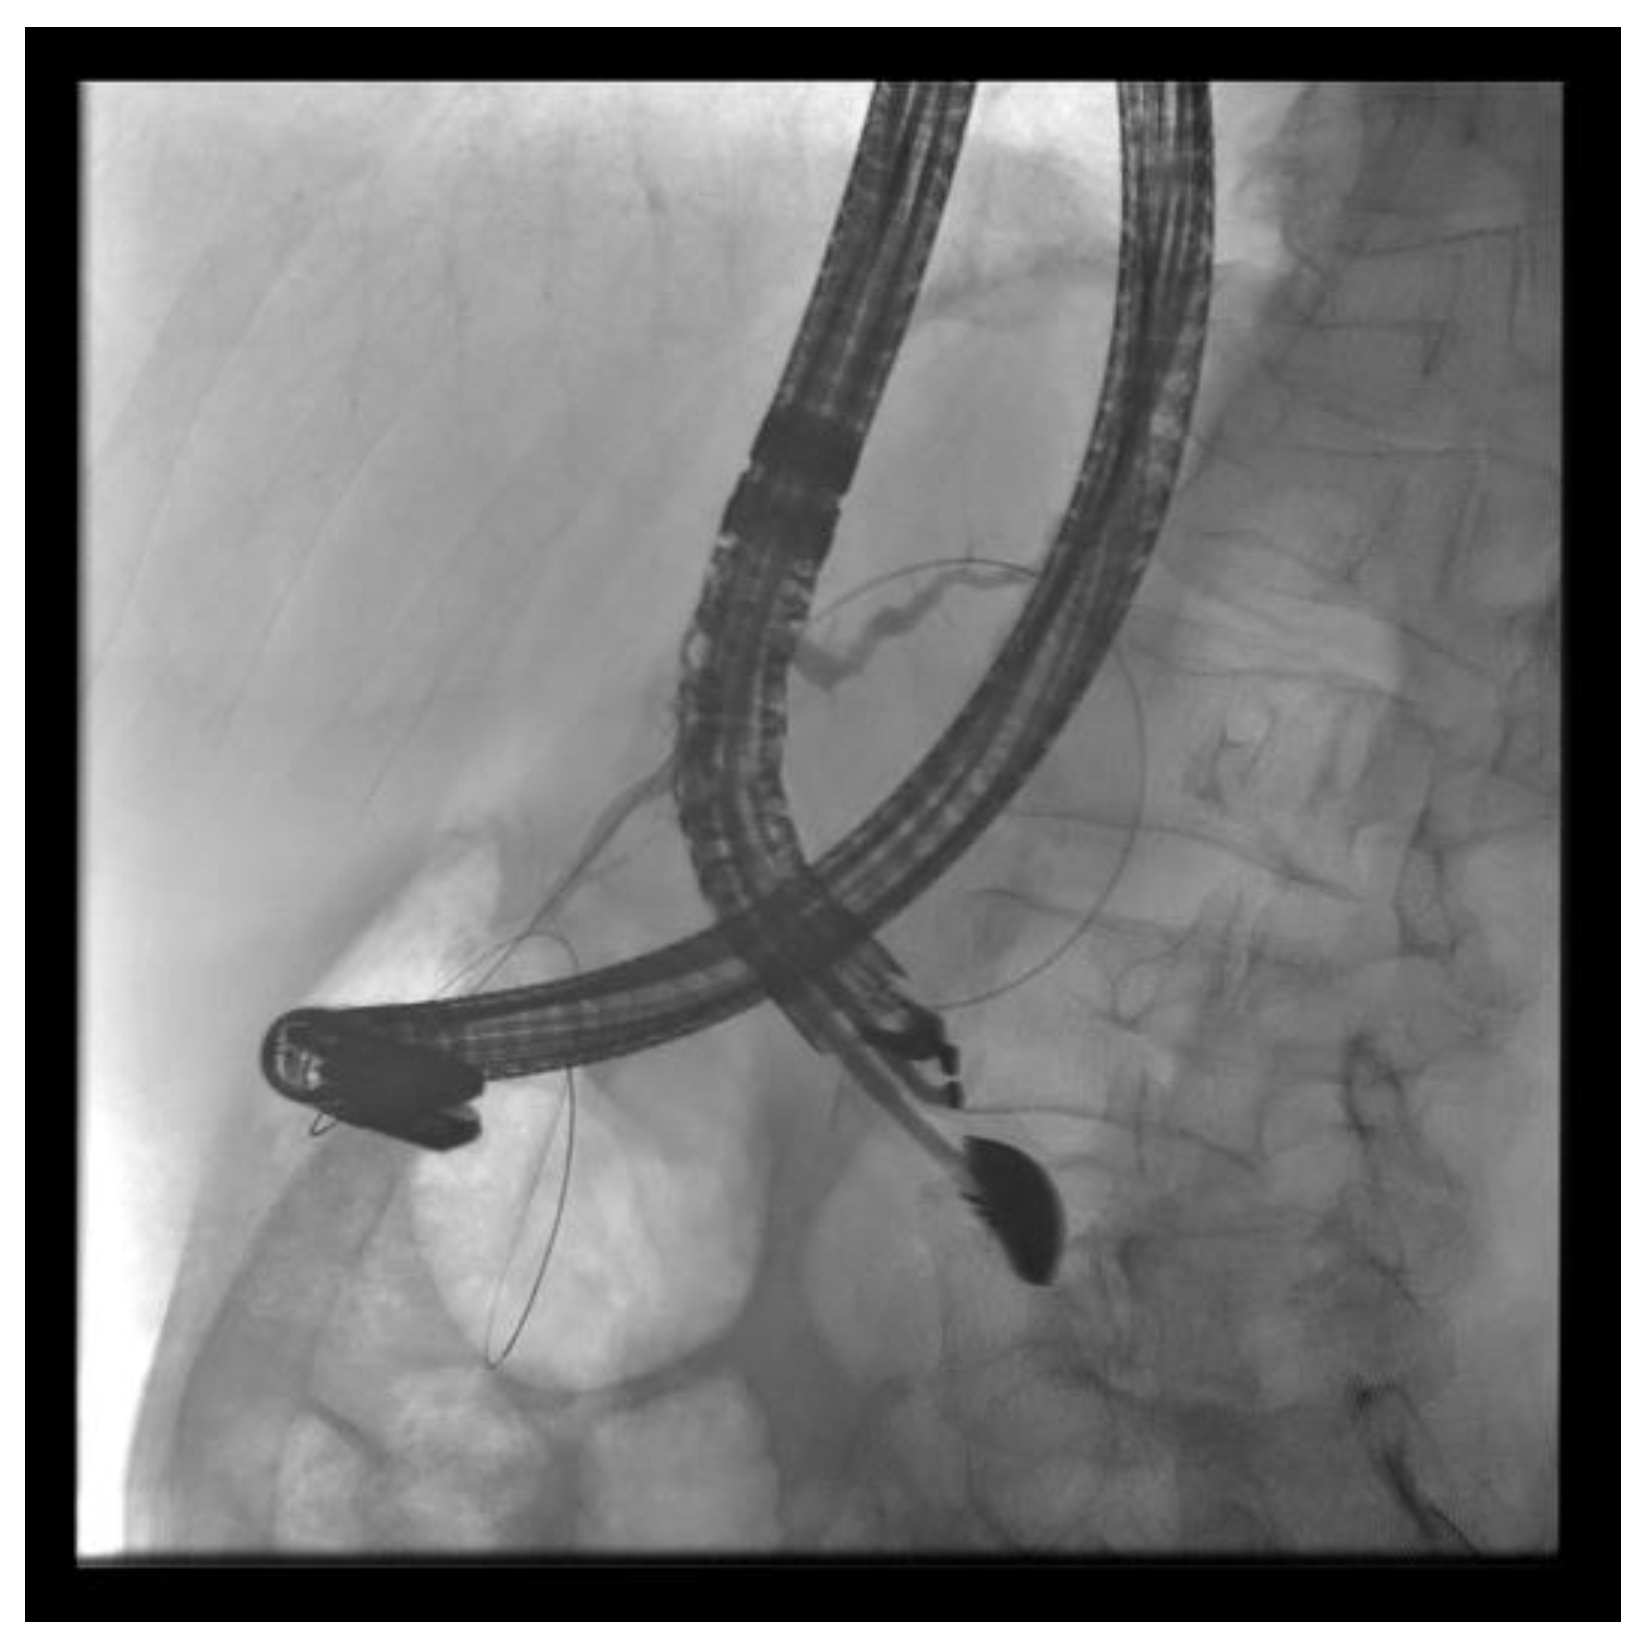

The patient is positioned prone on an X-ray fluoroscopy table and undergoes endoscopic ultrasound (EUS) using a therapeutic longitudinal scanner (e.g., EG 3270 UK, Hitachi Ultraschall, Berlin, Germany; GF-UCT 180, Olympus, Hamburg, Germany; Fuji EG-580UT2, Tokyo, Japan) following unsuccessful conventional ERP, with peri-interventional antibiotic administration i. v. (2 g ceftriaxone or 4 g tazobactam). Once the pancreatic duct is identified, a 19-G needle (Boston Scientific, Ratingen, Germany; Olympus, Hamburg, Germany) is used to puncture it in the direction of the anastomosis or papilla. Pancreatic juice is aspirated and sent for microbiological and cytological examination. Subsequently, the pancreatic duct is visualized via X-ray fluoroscopy following the instillation of the contrast medium (Figure 1 and Figure 2—selected from the clinical picture library of the reporting Dept. of Gastroenterology, Hepatology and General Internal Medicine as all the following figures).

Figure 2. Intraprocedural fluoroscopy (during EUS-guided procedure): Legend see also Figure 1.